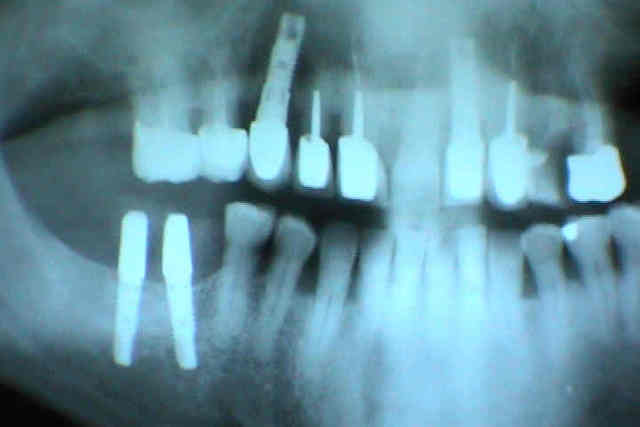

1er cas: une belle réussite chirurgicale et un massacre prothétique

2ème cas: une belle réussite prothétique(aucune mobilité, esthétiquement acceptable malgré la position des implants) et un massacre chirurgicale (6 ans)

ça vous convient comme échec?

mais ton cas n'est qu'un contre-temps pas vraiment une cata , celui d'alhoun est deja mieux .

Un aperçu de mes preferes